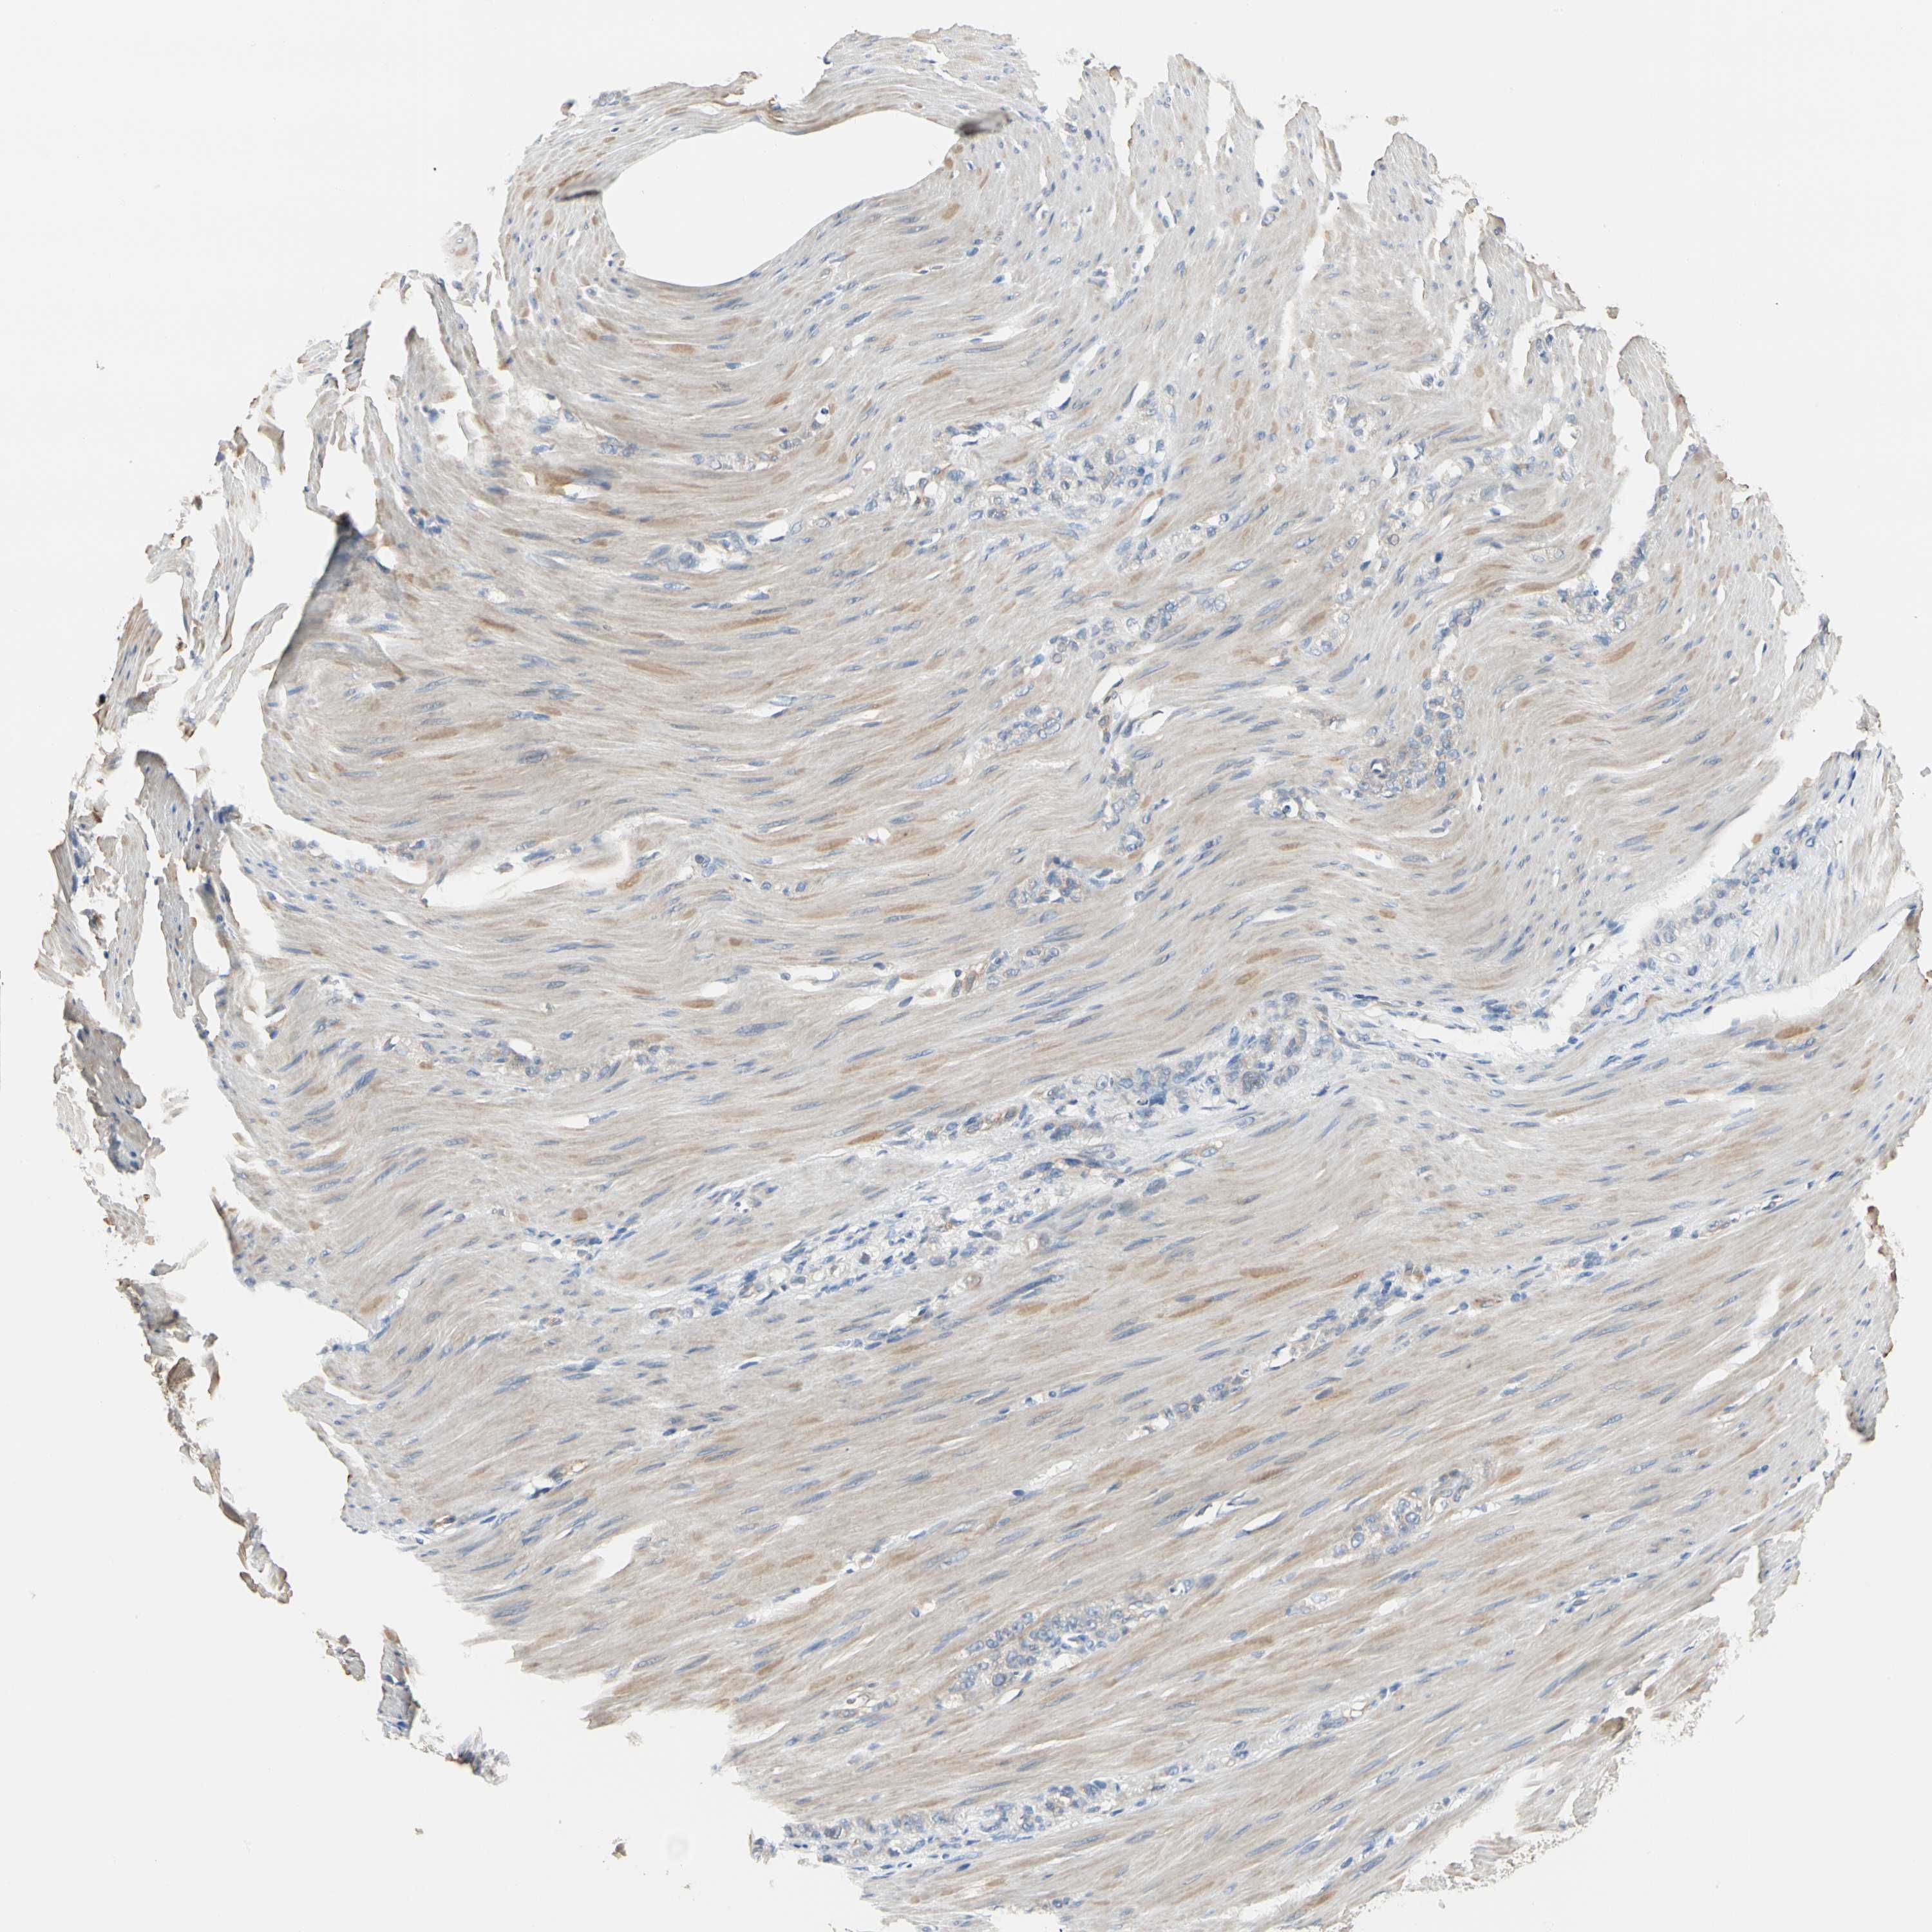

STOMACH CANCER - Protein expressioni

A mouse-over function shows sample information and annotation data. Click on an image to view it in a full screen mode. Samples can be filtered based on level of antibody staining by selecting one or several of the following categories: high, medium, low and not detected. The assay and annotation is described here.

Antibody stainingi

Antibody staining in the annotated cell types in the current human tissue is reported as not detected, low, medium, or high, based on conventional immunohistochemistry profiling in selected tissues. This score is based on the combination of the staining intensity and fraction of stained cells.

Each image is clickable and will lead to virtual microscopy that enables deeper exploration of all samples and also displays staining intensity scores, fraction scores and subcellular localization as well as patient and tissue information for each sample.

Antibody HPA007159

Staining

High

Medium

Low

Not detected

Intensity

Strong

Moderate

Weak

Negative

Quantity

>75%

75%-25%

<25%

None

Location

Nuclear

Cytoplasmic/membranous

Cytoplasmic/membranous,nuclear

Adenocarcinoma, NOS